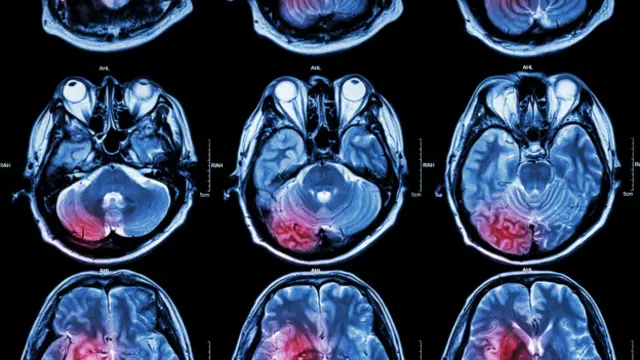

Neste caso, para poder identificar a atividade cerebral da paciente, os médicos inseriram eletrodos na parte posterior de sua cabeça, com o objetivo de medir a resposta do sistema nervoso central aos estímulos sensoriais, o que se conhece como "potencial visual evocado" (PEV).

"Normalmente, a informação viaja do olho até o tálamo (no centro do cérebro) e depois até a parte posterior, no córtex visual", diz o médico.

No entanto, os psiquiatras descobriram, graças a essa técnica, que a informação era "bloqueada" no cérebro de B.T. e não chegava a seu destino final.

"Esse caso mostra como o cérebro é capaz de bloquear informação e também revela que há uma base biológica nos transtornos visuais psicógenos e de múltiplas personalidades."